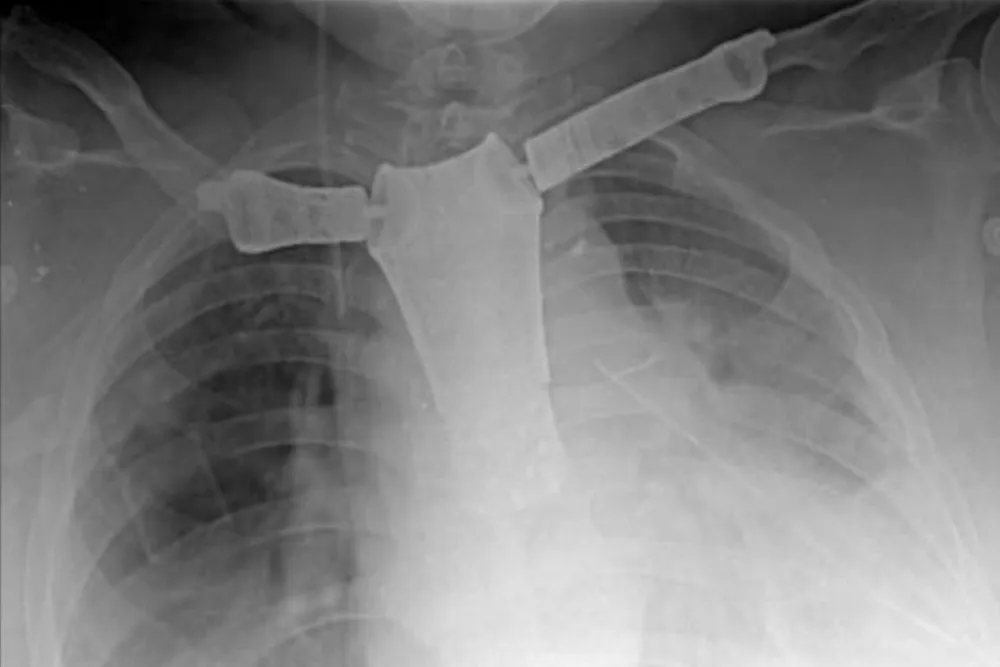

En este caso particular, una paciente de 61 años oriunda de Miramar fue operada, tras ser diagnosticada con un tumor en la pared torácica que afectaba el esternón, ambas clavículas y la primera costilla izquierda.

Cabe resaltar que se le realizó el reemplazo de esternón, clavícula y articulaciones con impresiones 3D.

La operación se realizó tras una exhaustiva evaluación preoperatoria y la confirmación del diagnóstico. Luego, se planificó una intervención que incluyó la extirpación del tumor y la reconstrucción de la pared torácica, preservando la movilidad de las clavículas.

Durante la cirugía, que tuvo una duración de 7.5 horas, se realizó la resección del tumor con márgenes oncológicos adecuados, seguida de la colocación de la prótesis y la cobertura con colgajos musculares.